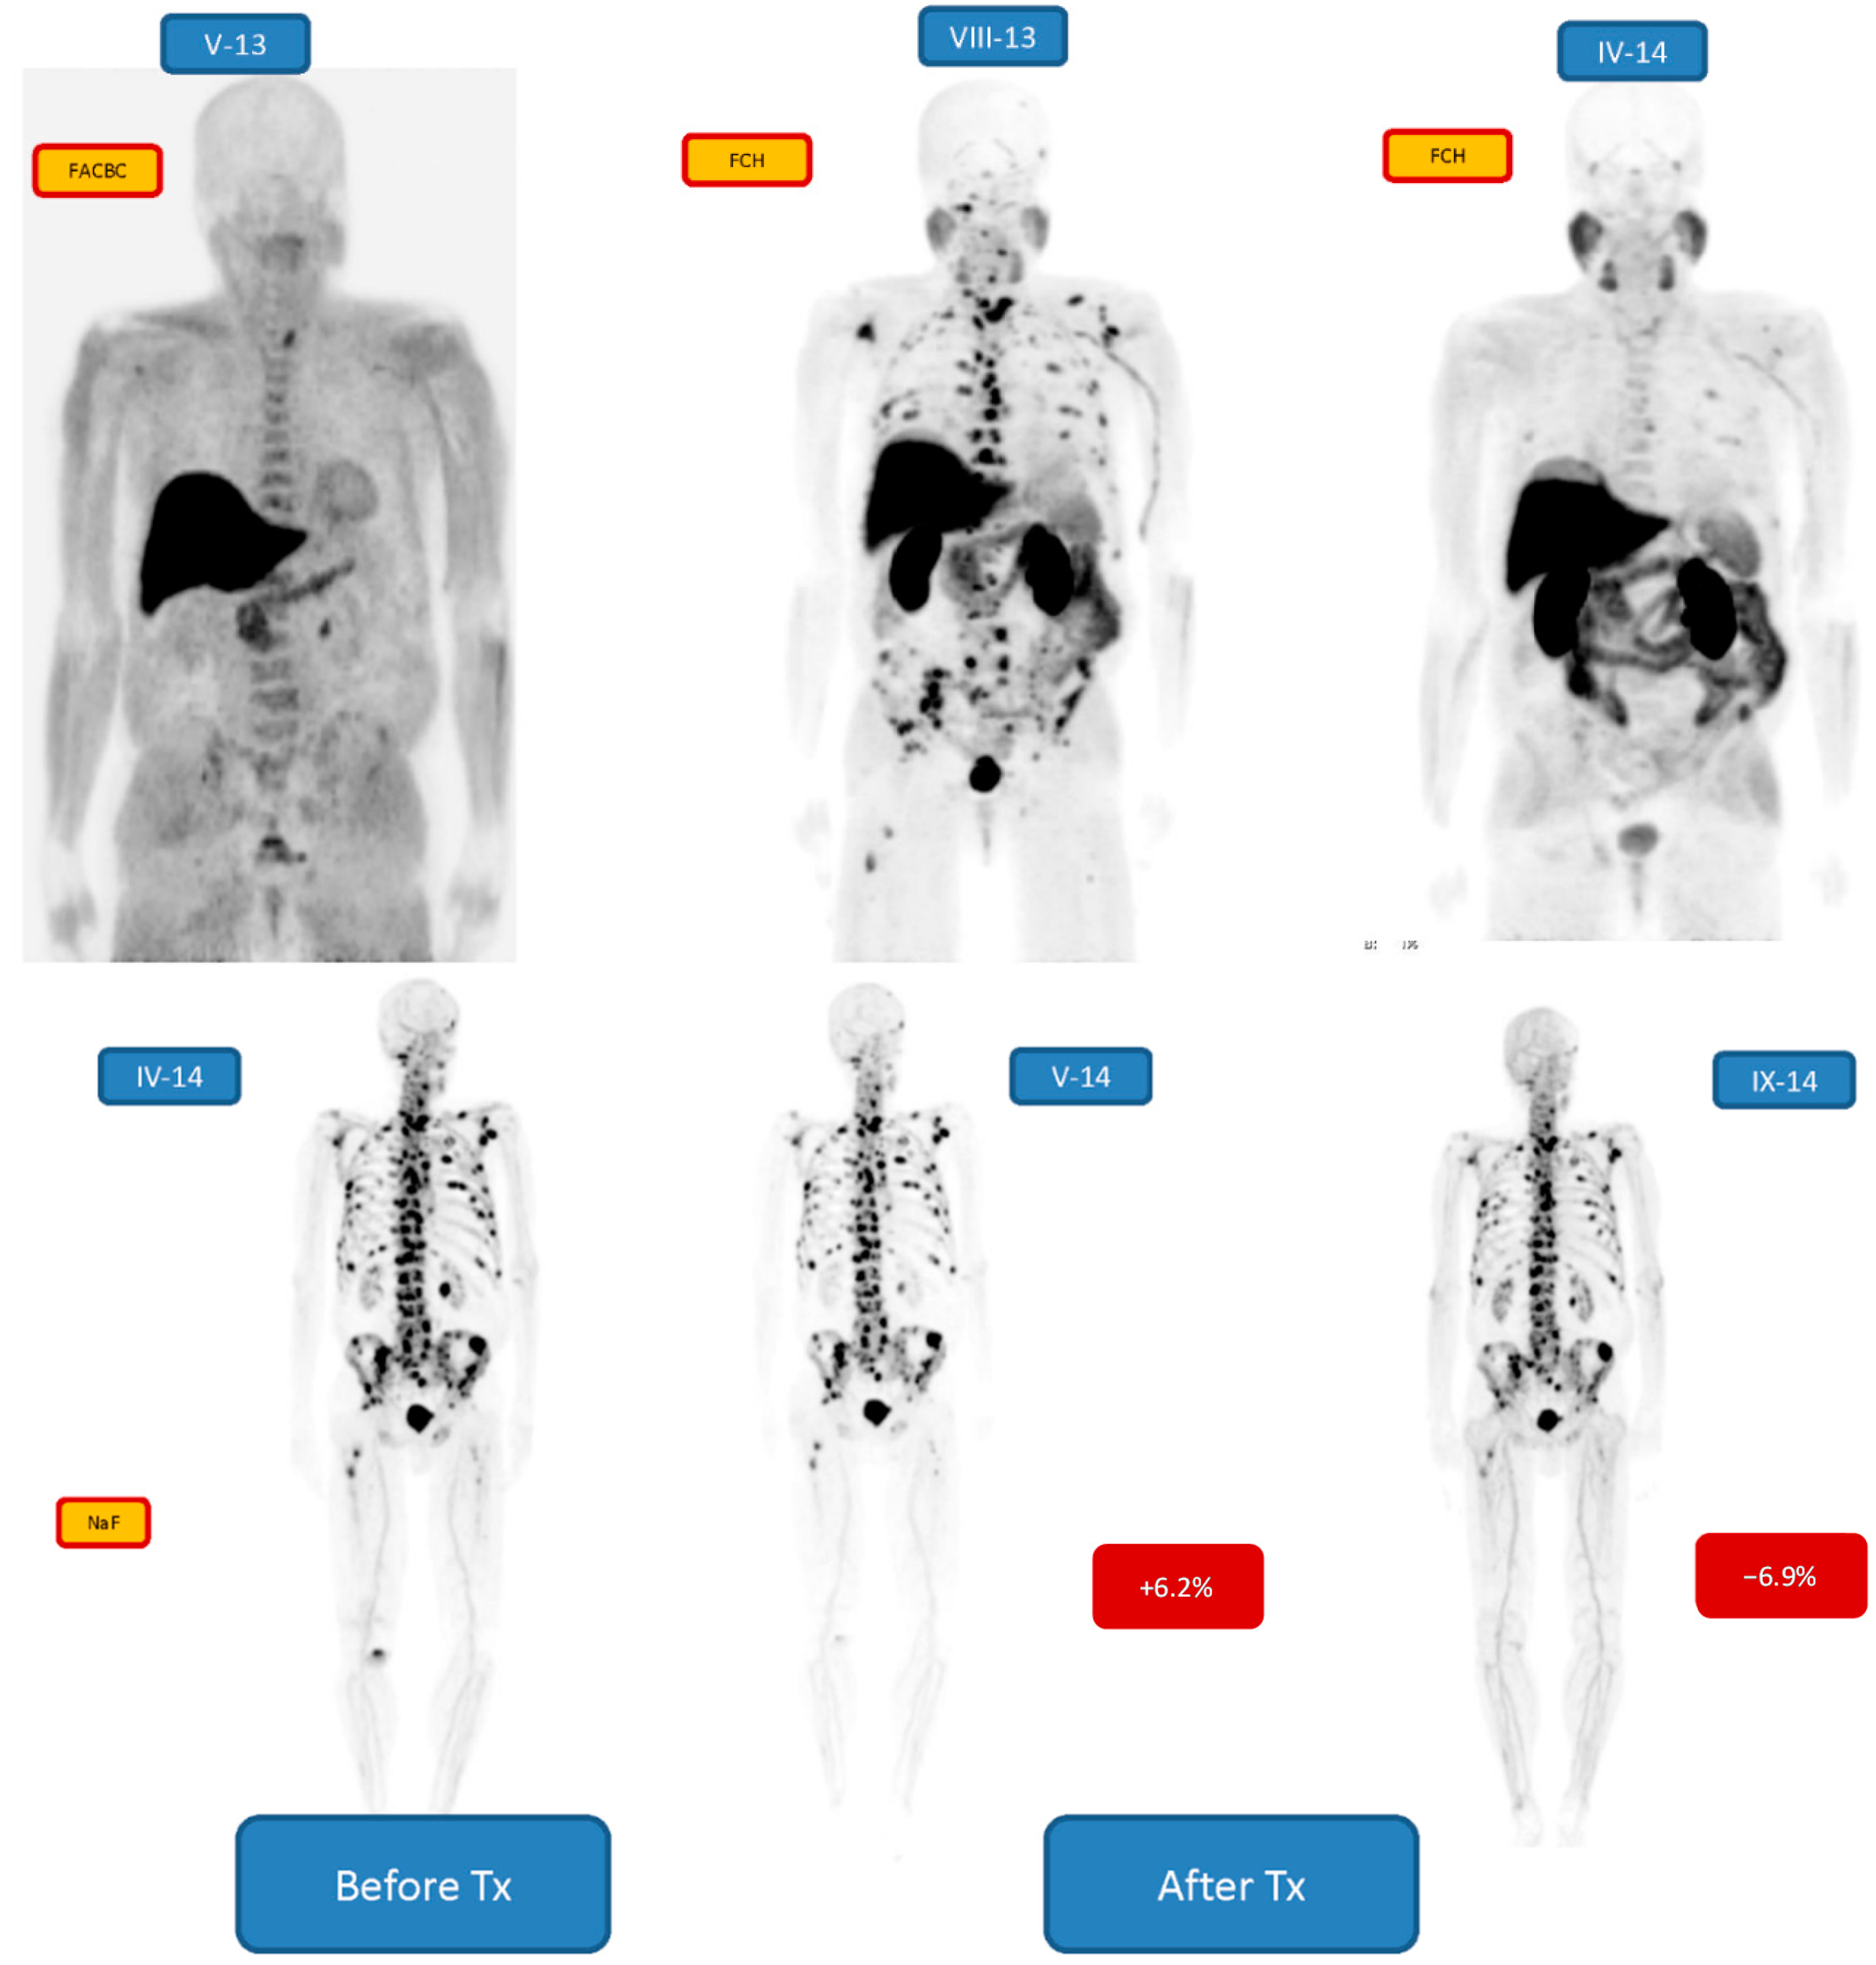

| 2 m/77 | Bone 2/3 | +6.2/−6.9 | 6 24.80 MBq | PR | Enzalutamide, Denosumab, Goserelin |

| 3 m/68 | Bone 3/3 | −10.8/−9.2 | 6 27.08 MBq | CR | Enzalutamide, Denosumab, Goserelin |